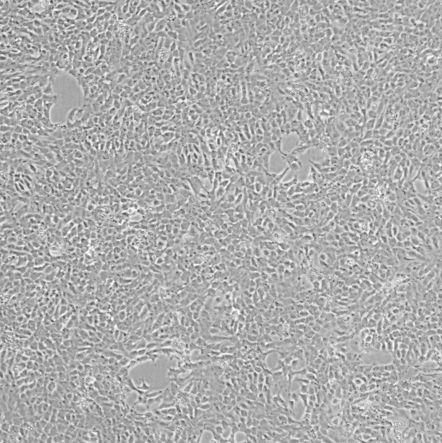

细胞形态:上皮样细胞

4T1 是从410.4瘤株中未经诱变筛得的6-硫鸟嘌噙抗性细胞株。当注射到BALB/c小鼠中时,4T1自发产生高转移肿瘤,可转移到肺,肝,淋巴结和大脑,同时在注射部位形成始发灶。诱导转移时不需要摘除始发灶。4T1细胞在BALB/c小鼠中的生长与转移特性与人体中的乳腺癌十分相近。这种肿瘤是人VI期乳腺癌的动物模型。4T1-诱导的肿瘤在手术后及未手术情况下转移的动力学相近,可以用作手术后及未手术模型。 跟其他肿瘤模型相比,由于4T1的抗6-硫鸟嘌噙特性,微小的转移细胞团(少到仅仅1个)也可以在许多远端器官中检测到。

该细胞通过慢病毒转染的方式携带Luc基因。